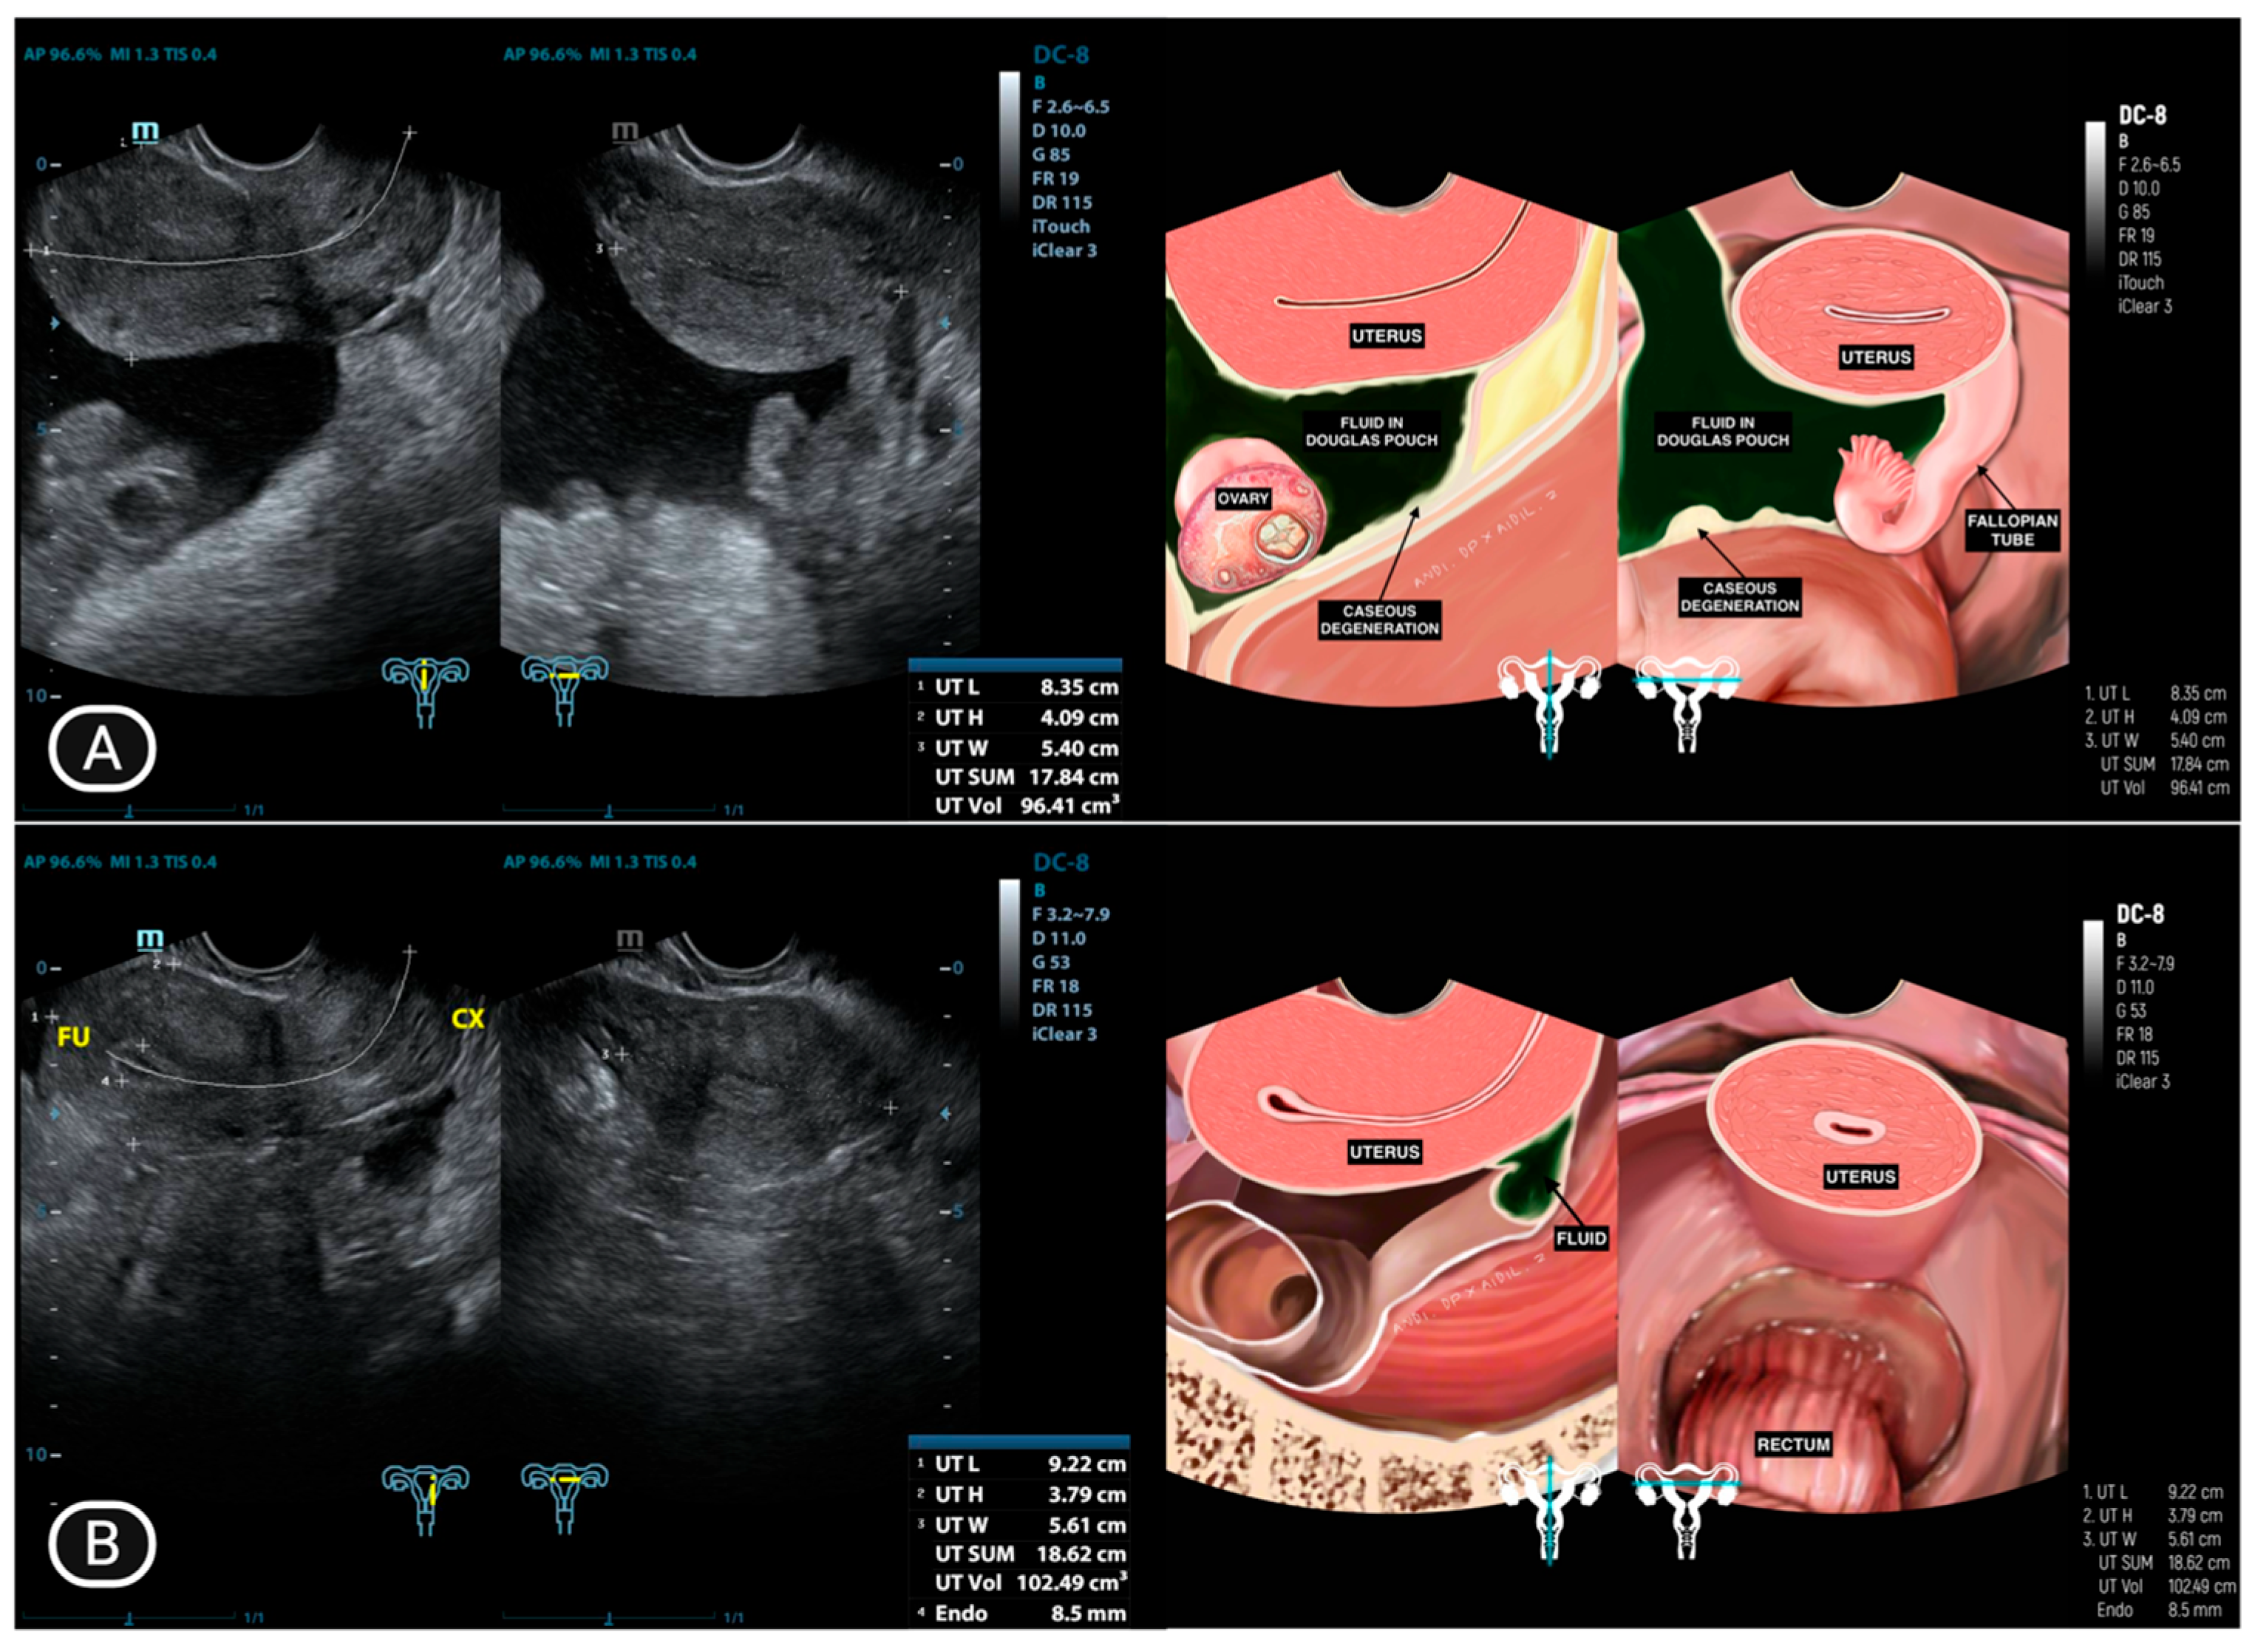

| 3 | IO (31) * | Caseous degeneration on the surface | Adhesion complex | Normal | Adhesion complex | Normal | (−) | Caseous degeneration on the surface of rectosigmoid colon and small bowel |

| 4 | SMK (29) * | Caseous degeneration on the surface. Complex fluid behind uterus | Normal | Not visualized | Adhesion complex with left fallopian tube | Hydrosalpinx | Complex fluid in cavum of Douglas with caseous degeneration | Caseous degeneration on the surface of rectosigmoid colon |

| 11 | Y (30) * | Normal | Adhesion to pelvic wall | Not visualized | Adhesion complex with left fallopian tube | Hydrosalpinx, filled with caseous degeneration inside | Complex ascites | (−) |

| 12 | DR (24) | Complex fluid in uterine cavity (10.98 mm) | Normal | Hydrosalpinx | Adhesion | Normal | (−) | (−) |